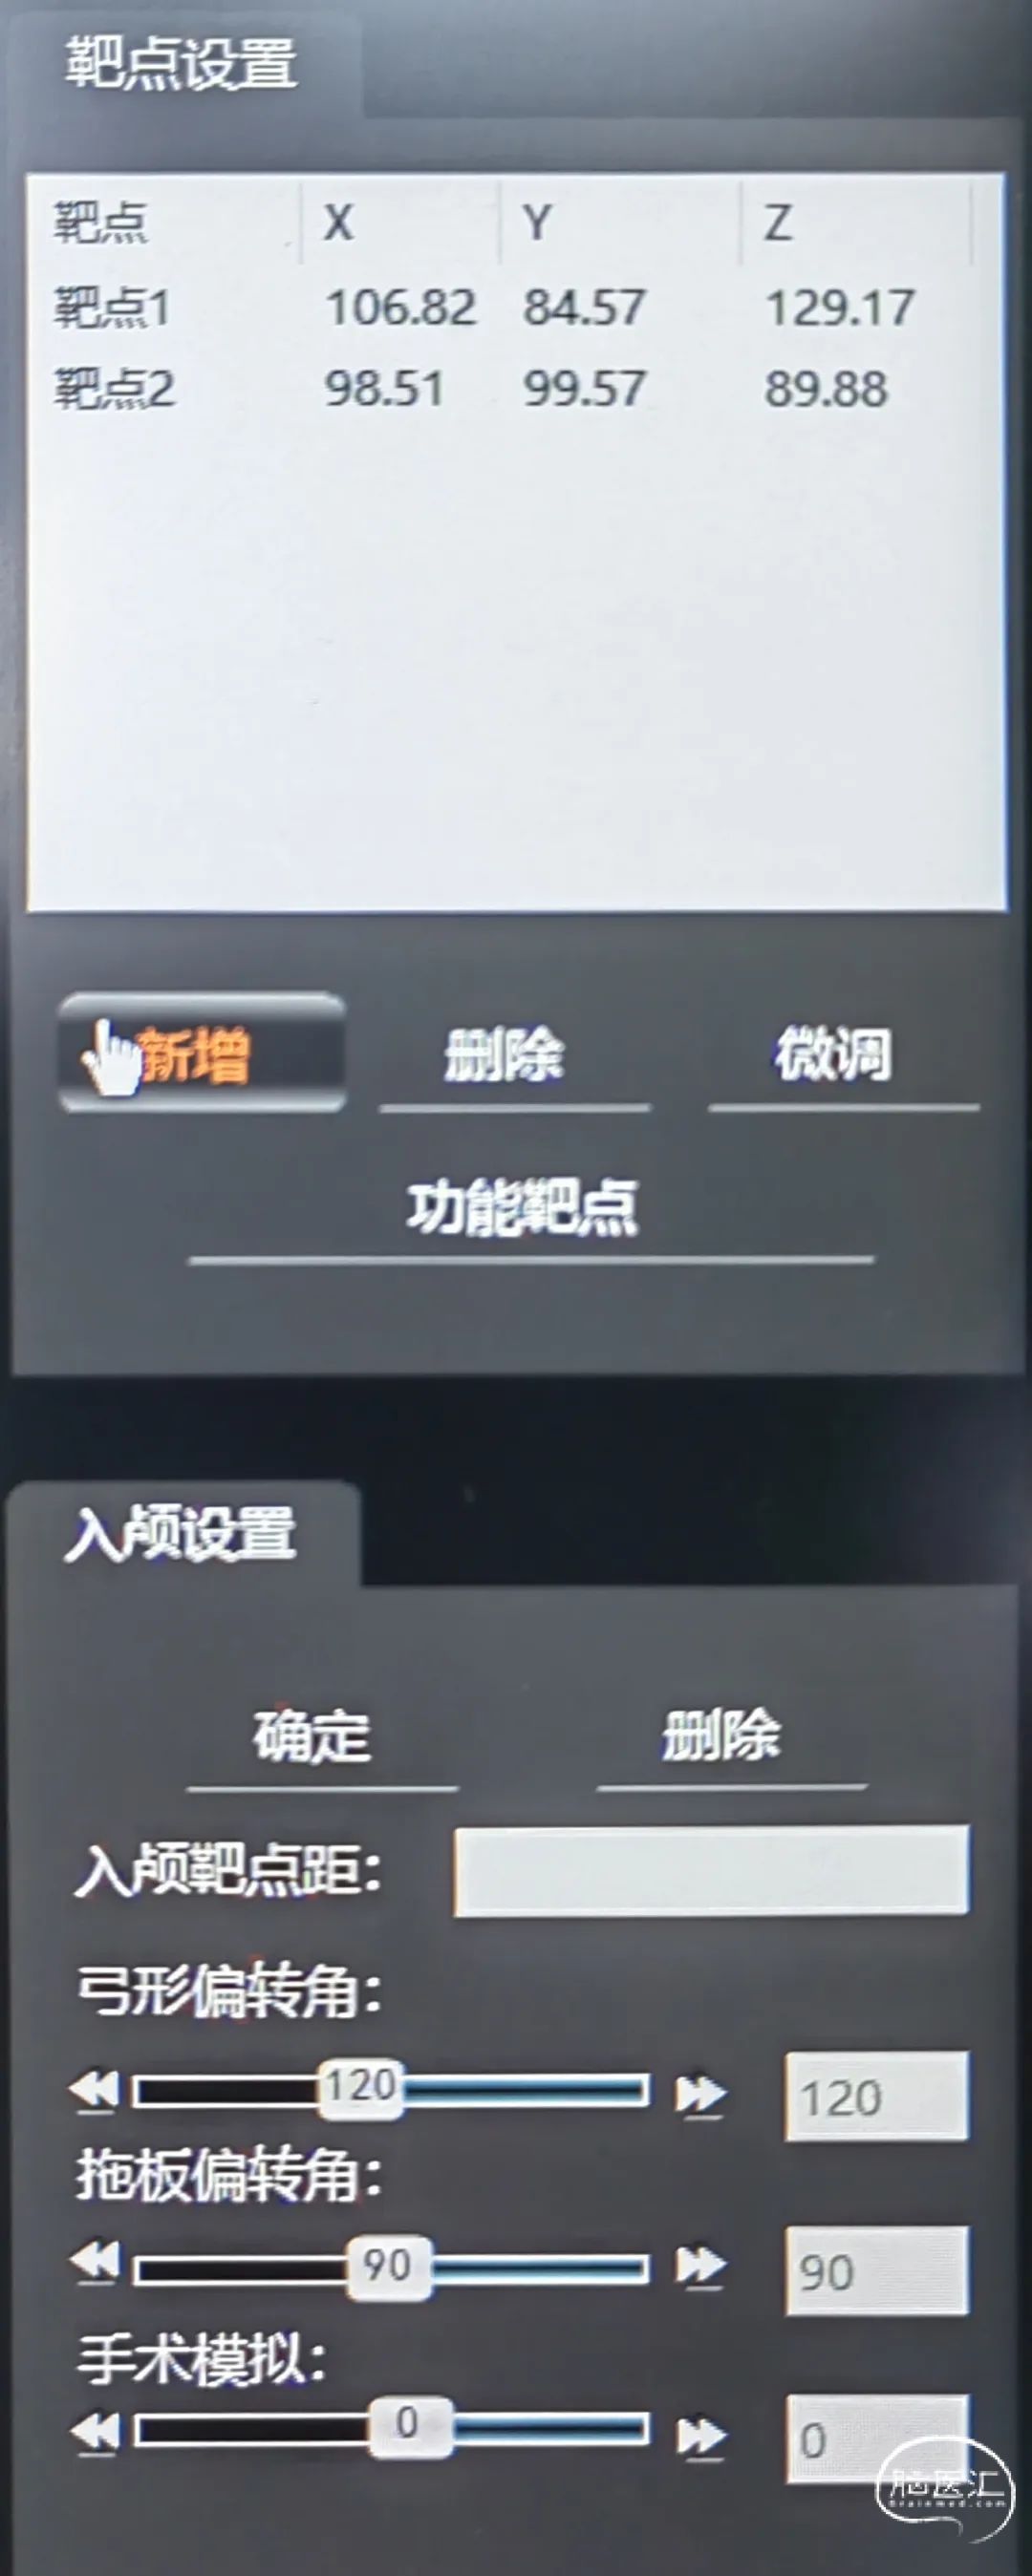

一口双孔,平行植入脑室引流管,测算脑室引流管植入靶点

双靶点